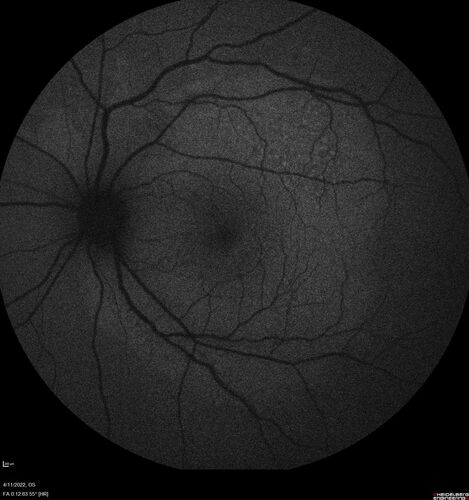

Acute Syphilitic Posterior Placoid Chorioretinitis

40 year old man About 10 days ago the patient woke up with a dark circle in the middle of the left eye that blocks his vision.  He thought it might be from fatigue.  The month of March was very stressful.  After a few days the spot in the left eye got darker and he could not drive at night.  During the last week while not going to work and sleeping more his vision is better but not normal.  He has never had vision loss in the past.

VA OD: sc20/16 NscJ1+VA OS: sc20/32+2 NscJ4

IOP: TP: OD:12 OS:12